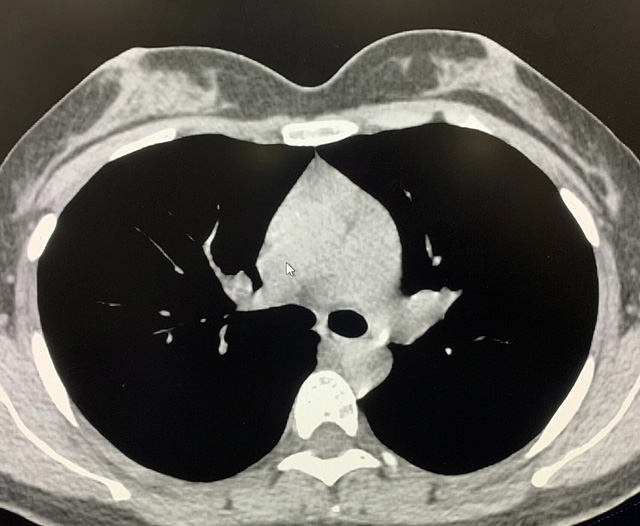

能譜純化技術(shù)的核心是通過(guò)物理濾過(guò)(如錫濾片)或軟件算法,選擇性濾除低能X射線光子,保留高能光子。在胸部低劑量CT掃描中顯著提升了圖像質(zhì)量與輻射劑量的平衡。

優(yōu)勢(shì)輻射劑量顯著降低相較于常規(guī)CT,輻射劑量減少約70%-90%,尤其適合需多次隨訪的高危人群(如肺癌篩查),降低輻射相關(guān)癌癥風(fēng)險(xiǎn)早期肺癌篩查效果明確可清晰檢測(cè)毫米級(jí)肺結(jié)節(jié),顯著提高早期肺癌檢出率,降低死亡率。檢查快捷且普及性高單次掃描僅需數(shù)秒,無(wú)需對(duì)比劑,設(shè)備廣泛配置于基層醫(yī)院,便于大規(guī)模篩查。長(zhǎng)期成本效益顯著雖單次費(fèi)用與常規(guī)CT相近,但早期干預(yù)可大幅降低晚期治療費(fèi)用及社會(huì)醫(yī)療負(fù)擔(dān)。技術(shù)優(yōu)化提升圖像質(zhì)量迭代重建算法(如ASIR、MBIR)在降低劑量同時(shí)減少噪聲,平衡影像質(zhì)量與安全性。